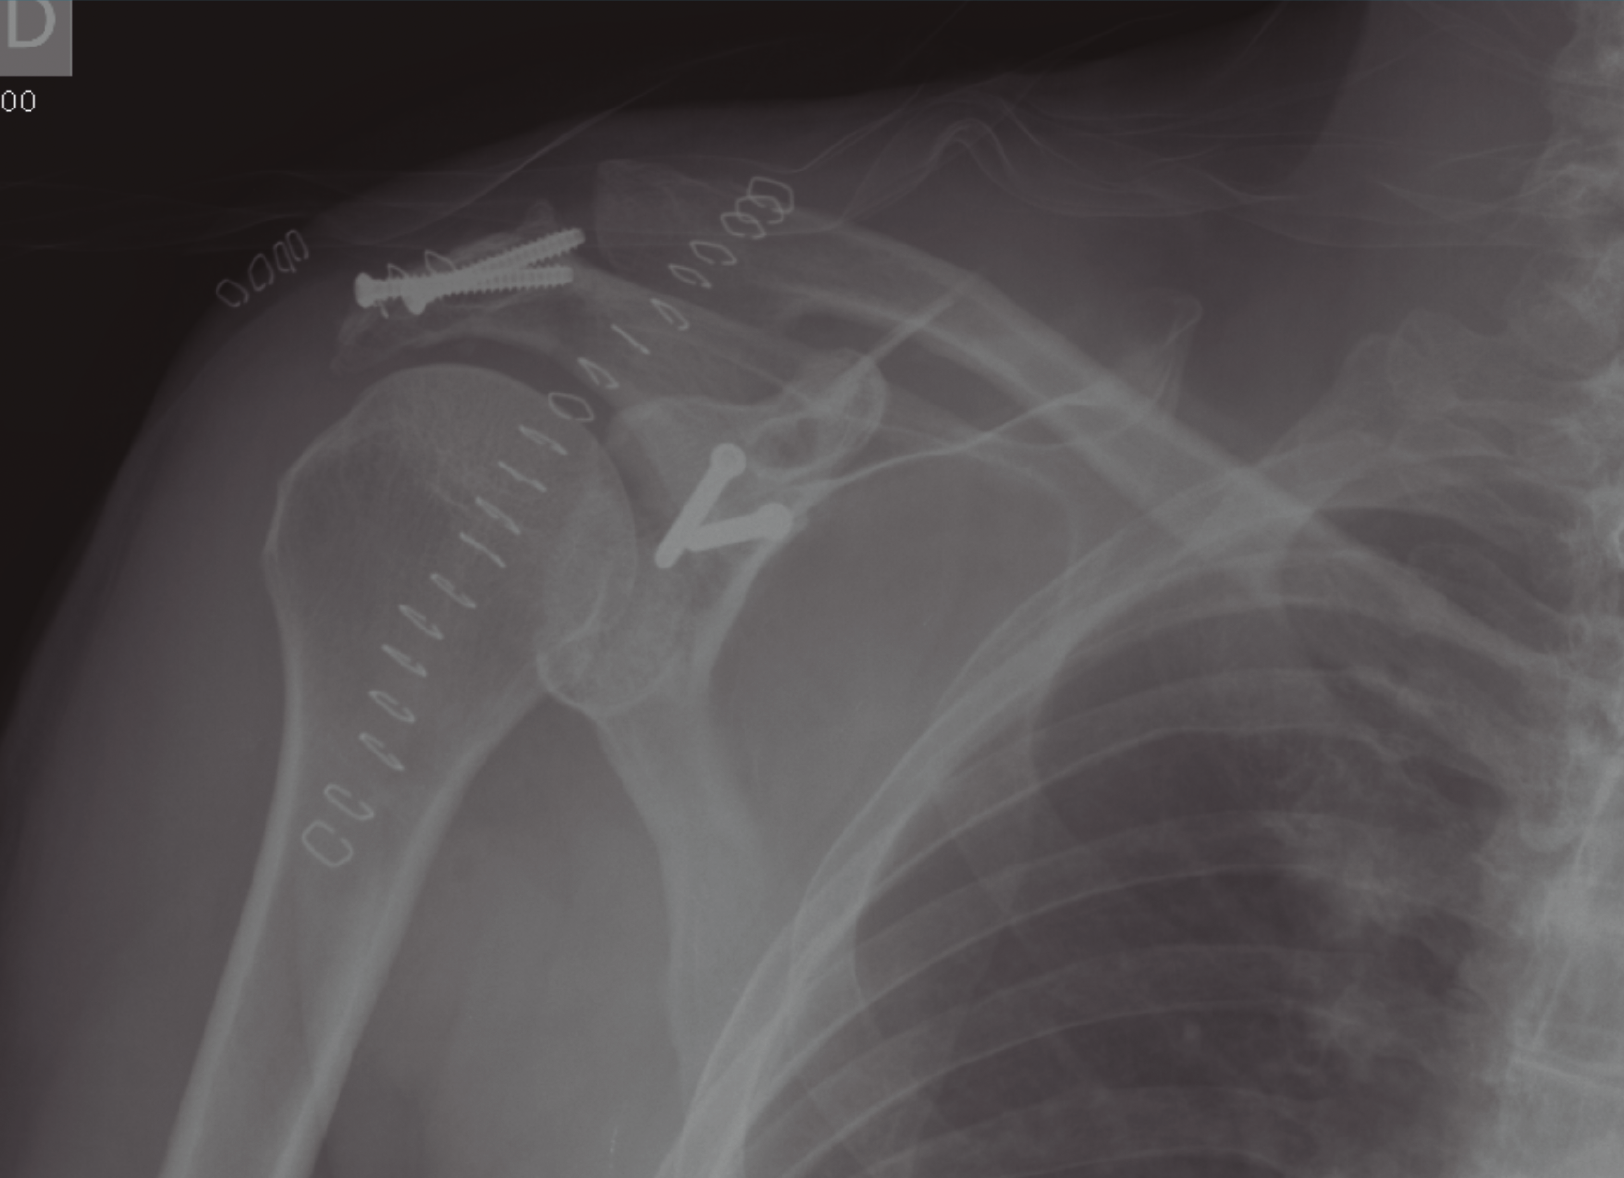

La cirugía se lleva a cabo a las 2 semanas del ingreso, dado que el estado del paciente no la permitía. Se llevó a cabo la reducción abierta y la estabilización de la fractura de la fosa glenoidea con 2 tornillos canulados mediante un abordaje deltopectoral (Figura 3).

Figura 3. Imagen postoperatoria donde se observa la síntesis de la glena y del acromion con tornillo canulados.